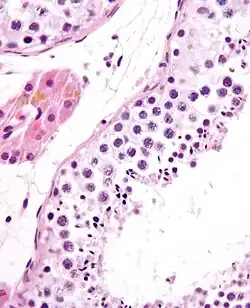

Seminiferous tubule in cross-section (large tubular structure – center of image) with sperm (black, tiny, ovoid bodies furthest from the outer edge of the tubular structure). H&E stain.

The epithelium of the tubule consists of a type of sustentacular cells known as Sertoli cells, which are tall, columnar type cells that line the tubule.

In between the Sertoli cells are spermatogenic cells, which differentiate through meiosis to sperm cells. Sertoli cells function to nourish the developing sperm cells. They secrete androgen-binding protein, a binding protein which increases the concentration of testosterone.